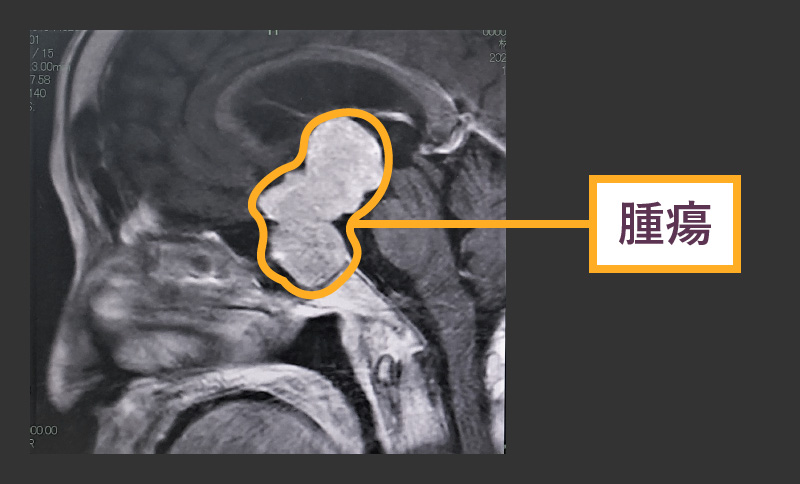

下垂体は、鼻橋の後ろ、脳の下にある小さな腺です。この腺の周囲の腫瘍はさまざまな種類の頭痛を引き起こす可能性がありますが、額に痛みを引き起こすことがよくあります。

ほとんどの下垂体腫瘍は良性であり、癌性ではありません。しかし、それらが脳や神経の一部を圧迫したり、ホルモンを生成したりすると、さまざまな症状を引き起こす可能性があります。

下垂体腫瘍による頭痛は、頭の前部、額の周囲、または目の後ろに現れることがよくあります。人が経験する痛みの正確な場所と種類は、腫瘍の大きさ、腫瘍が成長している場所、腫瘍が影響を与える周囲の組織によって異なります。ただし、この病気のすべての人が症状を経験するわけではありません。